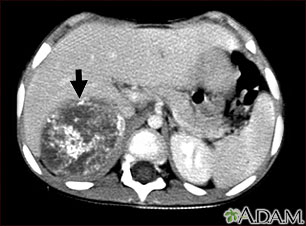

Tomografía computarizada de neuroblastoma en el hígado

Esta TC del abdomen superior muestra un tumor grande (neuroblastoma) en el lado derecho del abdomen del paciente (lado izquierdo inferior de la imagen). El tumor se encuentra detrás del hígado, empujándolo hacia adelante, y existe la posibilidad de que se disemine dentro del tejido hepático.